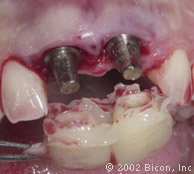

Произведены послабляющие разрезы

Установка готовых конструкций